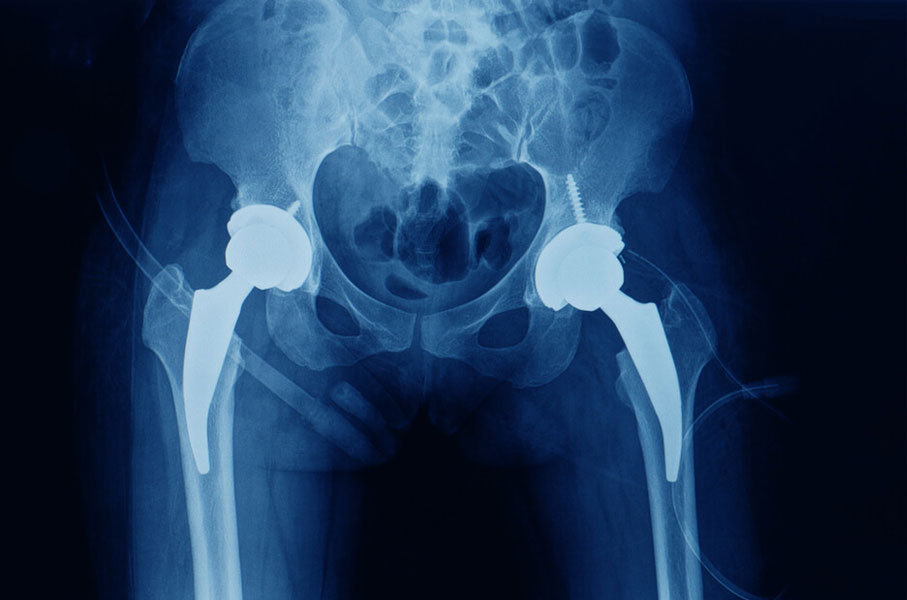

A NBR 15719 de 01/2023 - Implantes para ortopedia — Prótese de quadril — Requisitos para prótese acetabular estabelece requisitos para materiais, fabricação, avaliação de projeto, avaliação de desempenho, marcação, embalagem, rotulagem e esterilização, bem como identifica os tipos de prótese, a designação de dimensões e atributos de projeto e o desempenho pretendido de próteses acetabulares. Não se aplica às próteses acetabulares fabricadas sob medida (projetadas individualmente para um único paciente), de revisão ou constritas. A prótese acetabular, em artroplastia de quadril é destinada a substituir o acetábulo biológico na artroplastia total de quadril. A prótese acetabular compreende a superfície de suporte articular acetabular e a superfície de fixação à estrutura óssea acetabular. Em uma prótese acetabular modular, o sistema é composto pelo suporte acetabular e pelo inserto acetabular